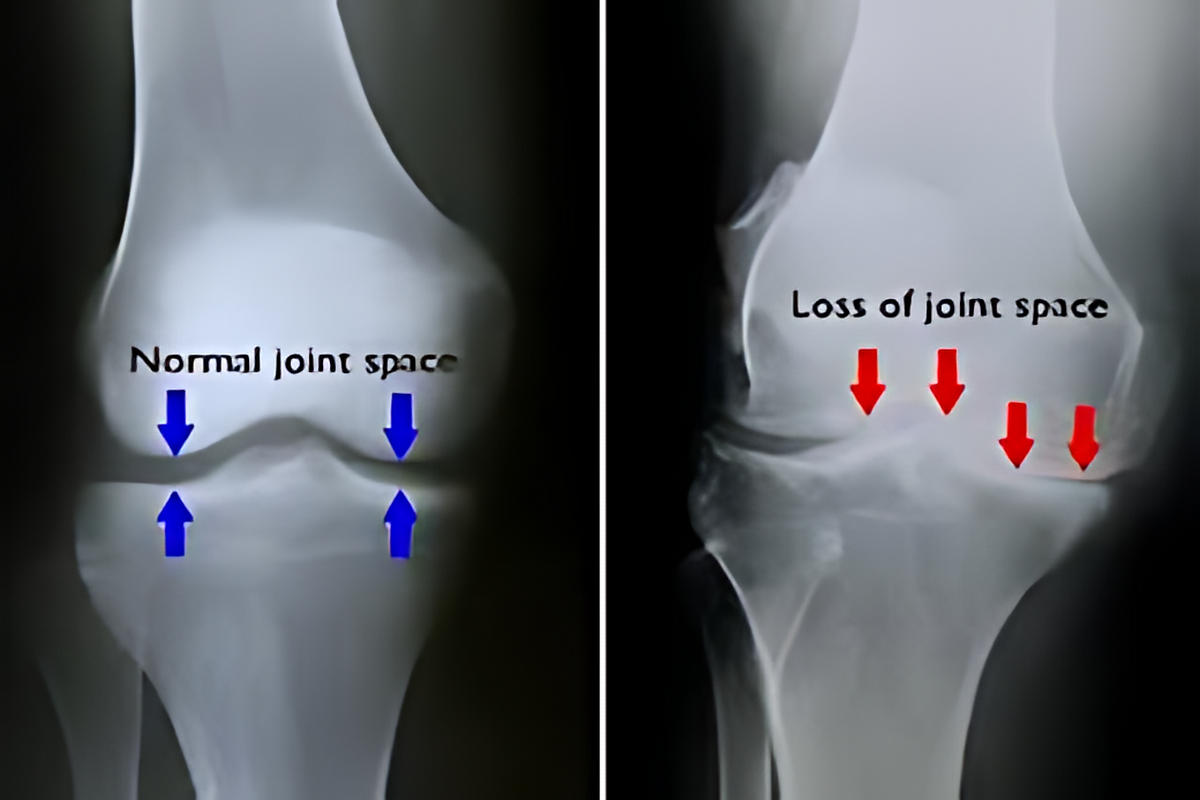

Η αρθρίτιδα είναι μία εκφυλιστική και συχνά φλεγμονώδης πάθηση της άρθρωσης, κατά την οποία καταστρέφεται σταδιακά ο αρθρικός χόνδρος. Η απώλεια του χόνδρου οδηγεί σε άμεση τριβή των οστών μεταξύ τους, προκαλώντας πόνο, δυσκαμψία και, σε προχωρημένα στάδια, παραμόρφωση της άρθρωσης.

Το πιο συχνό σύμπτωμα είναι ο πόνος στο γόνατο, ιδιαίτερα κατά την κίνηση ή τη φόρτιση. Πολλοί ασθενείς αναφέρουν δυσκαμψία μετά από ξεκούραση ή τις πρωινές ώρες, καθώς και οίδημα της άρθρωσης.

Κατά την κίνηση μπορεί να ακούγεται ή να γίνεται αισθητό «τρίξιμο», ενώ στα προχωρημένα στάδια εμφανίζεται παραμόρφωση του γόνατος και σημαντικός περιορισμός της κινητικότητας.